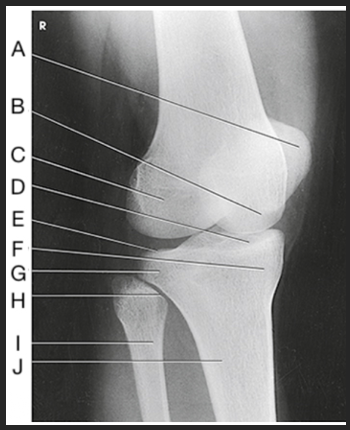

Name this projection

AP knee

Where does the CR enter for this projection?

½" inferior to patellar apex

If the patient is sthenic (19-24 cm) how is the CR directed?

0 degrees (perpendicular to IR)

Label the image: A

femur

Label the image: B

patella

Label the image: C

lateral femoral epicondyle

Label the image: D

lateral femoral condyle

Label the image: E

Lateral tibial plateau

Label the image: F

intercondylar eminence

Label the image: G

head of fibula

Label the image: H

tibia

Label the image: I

fibula